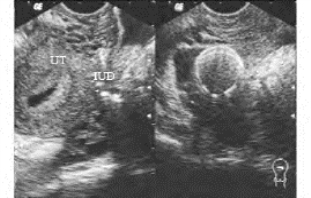

2.子宫穿孔、节育器异位 多因术者技术原因而将节育器放置于子宫穿孔部位引起,常从宫角或子宫峡部穿孔。若节育器异位紧靠子宫周围时,凭借节育器特殊形态的强回声及伴后方“彗星尾”征,可诊断之。如节育器异位处因子宫周围肠腔气体干扰,超声诊断较困难,可结合X线或CT检查(图33-19B)。

图33-19B 子宫穿孔节育器嵌于子宫直肠窝声像图